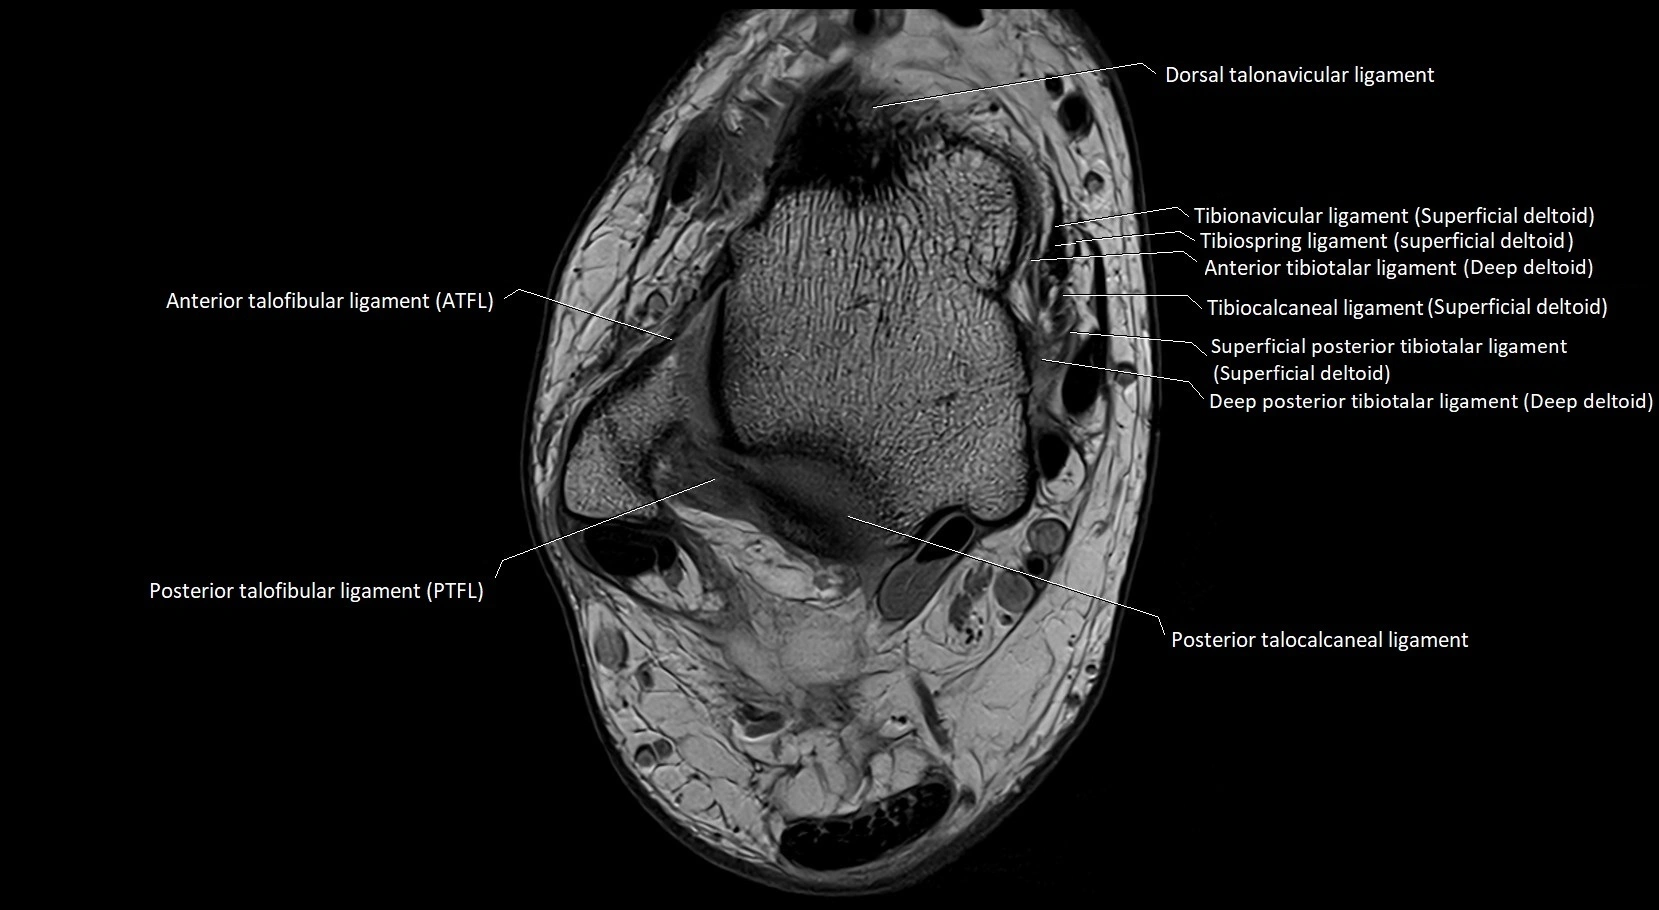

MRI image

image